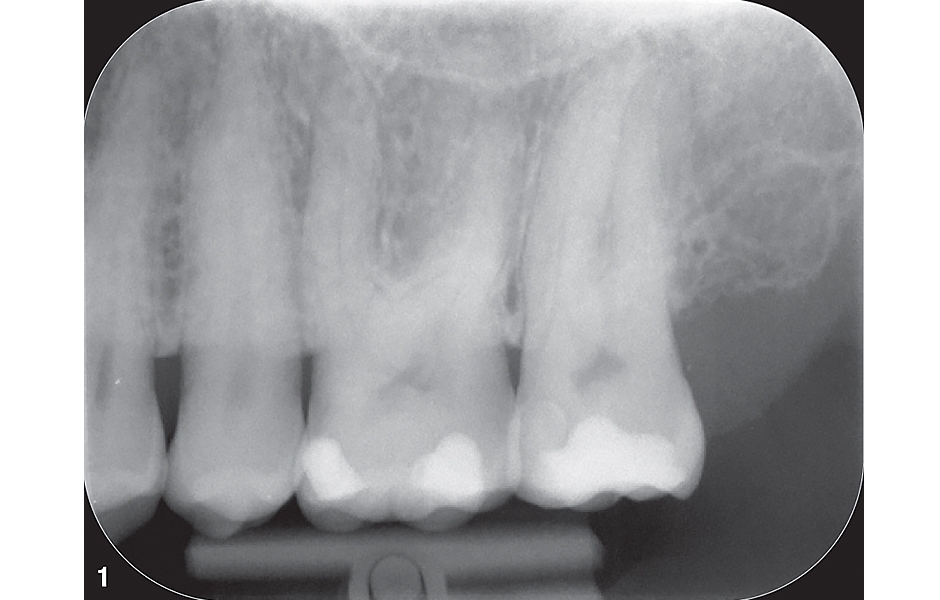

V únoru 2024 se do naší ordinace dostavila 46letá pacientka se silnou bolestí v levé horní čelisti. Po pozitivním testu vitality a silné reakci na poklepový test byla rentgenologicky potvrzena diagnóza ireverzibilní pulpitidy zubu č. 27 (obr. 1). Pacientka souhlasila s ošetřením kořenového kanálku ve dvou návštěvách – ošetření bylo zahájeno v rámci první návštěvy.

Obr. 1: Předoperační rentgenový snímek zubu 27.